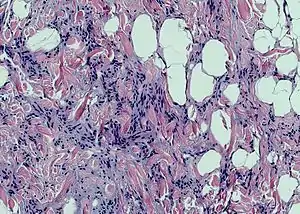

Spindle cell lipoma

Spindle cell lipoma is an asymptomatic, slow-growing subcutaneous tumor that has a predilection for the posterior back, neck, and shoulders of older men.[1]:625[2]